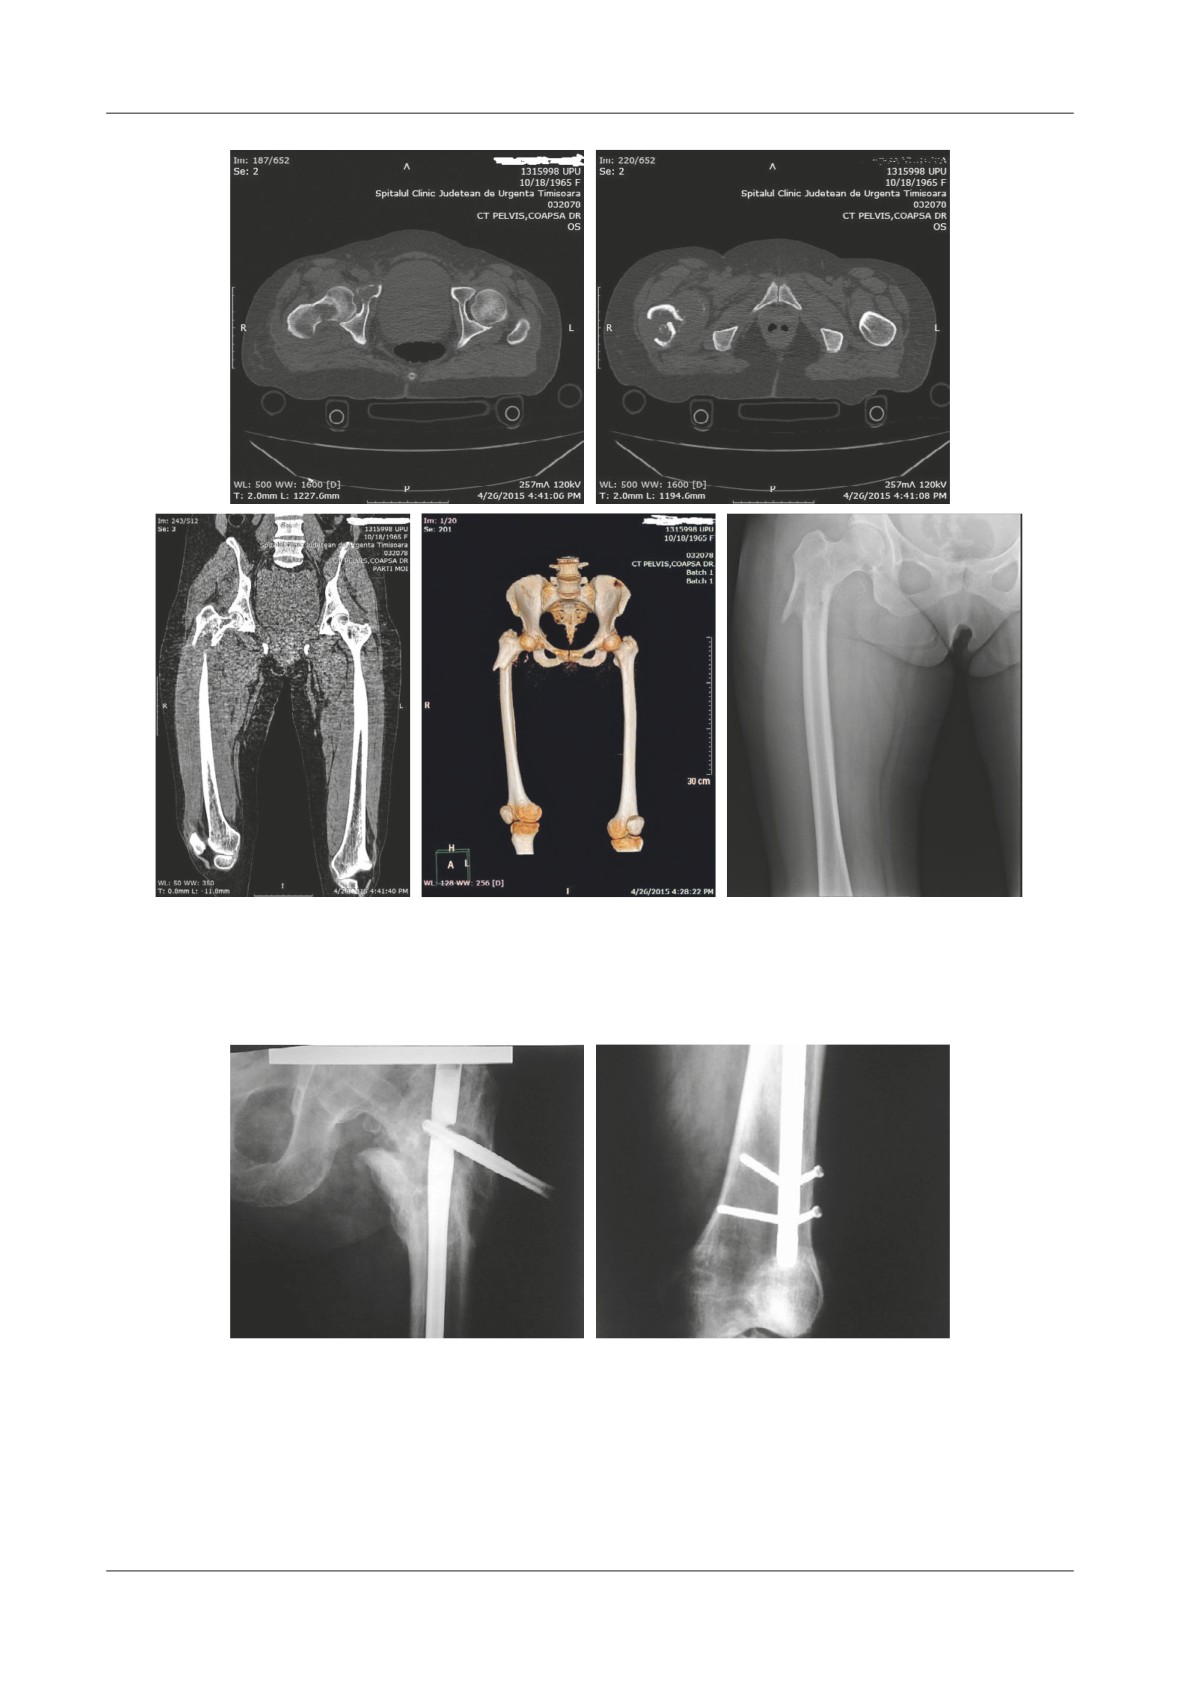

Axial CT images obtained after admittance reveal the

level.

lytic bone area from within the femoral neck as well as

the zone of the pathologic fracture. Coronal CT

Material and Methods

reconstruction shows the tumor mass that expands the

muscles surrounding the proximal femoral area. CT

We performed a search in the County Hospital’s

reconstruction meant to carefully show if there are any

electronic database searching for patients admitted with

Figure 2. A,B. Axial CT images that reveal the lytic bone area from within the femoral neck as well as the zone

of the pathologic fracture. C. Coronal CT reconstruction shows the tumor mass that expands the muscles

surrounding the proximal femoral area. D. 3D CT reconstruction meant to carefully show if there are any

other fractures that expand distally. E. AP X-ray of the right coxo-femural joint

Figure 6. A. Initial AP X-ray of the pelvis which reveals the un displaced fracture. B. 2 weeks later the fracture has become displaced

and requires surgical care. C. Te postoperative X-ray reveals proper fixation of the implant and early mobilization is indicated